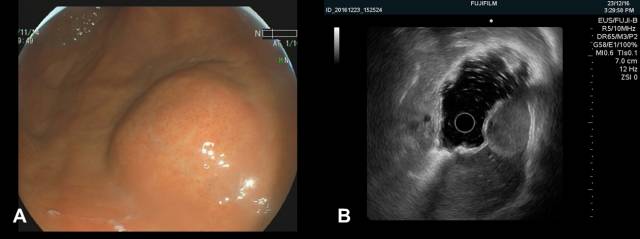

1.肝囊肿外压

胃底肝左叶区域可见粘膜下半球形隆起,表面光滑(图 A),EUS见类圆形无回声病灶外压,其后方回声增强,可见囊性病灶特有的双侧折射声影(图B白箭头),故诊断为肝左叶囊肿外压。